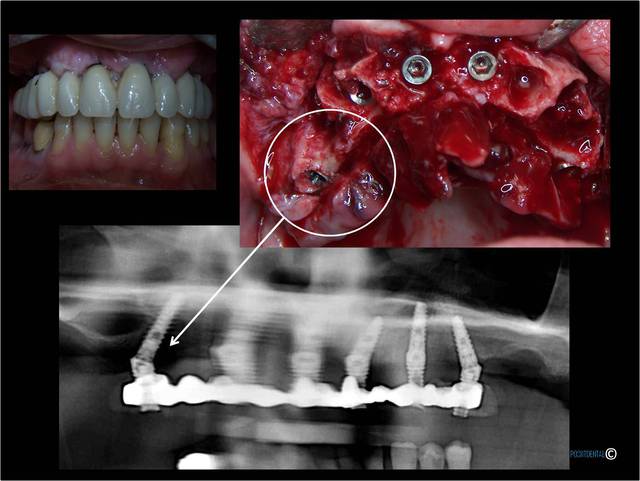

NB : les PAC ne sont pas du tout équilibrées, mais stables. Un implant à foiré en secteur 3 et à été remplacé (retiré sans anesthésie, elle a vue les étoiles ...)

A la mandibule :

Au maxillaire , même moi qui ne suis qu'un petit , petit omnipraticien , et surtout pour le dernier à droite d'implant c'est hallucinant et avec mon expérience en bricolage , bin ce all on5 et demi me fait peur . Je ne vois pas pourquoi virer un bloc antérieur et ne pas profiter des alvéoles de chaque dent , en postérieur attendons que Pp très au fait revienne .